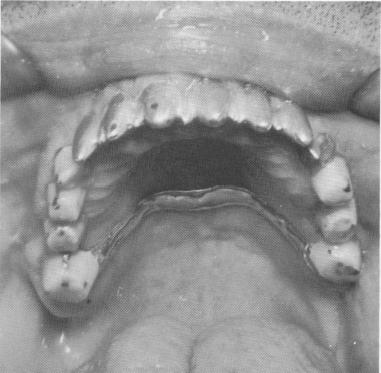

Three vent-plants were placed in the anterior quadrant: one in each lateral incisor region, and one in the nasal septum (Fig. 4-33). A full-arch scalloped template—with a posterior palatal bar—was cast to fit passively over the soft tissue covering the crest of the alveolar ridge. Anteriorly the template contained three copings that fitted over the protruding shafts of the vent-plants.

Fig. 4-33. Clinical view of the anterior vent-plants.

1 Clinical view of anterior vent-plant endosseous implant